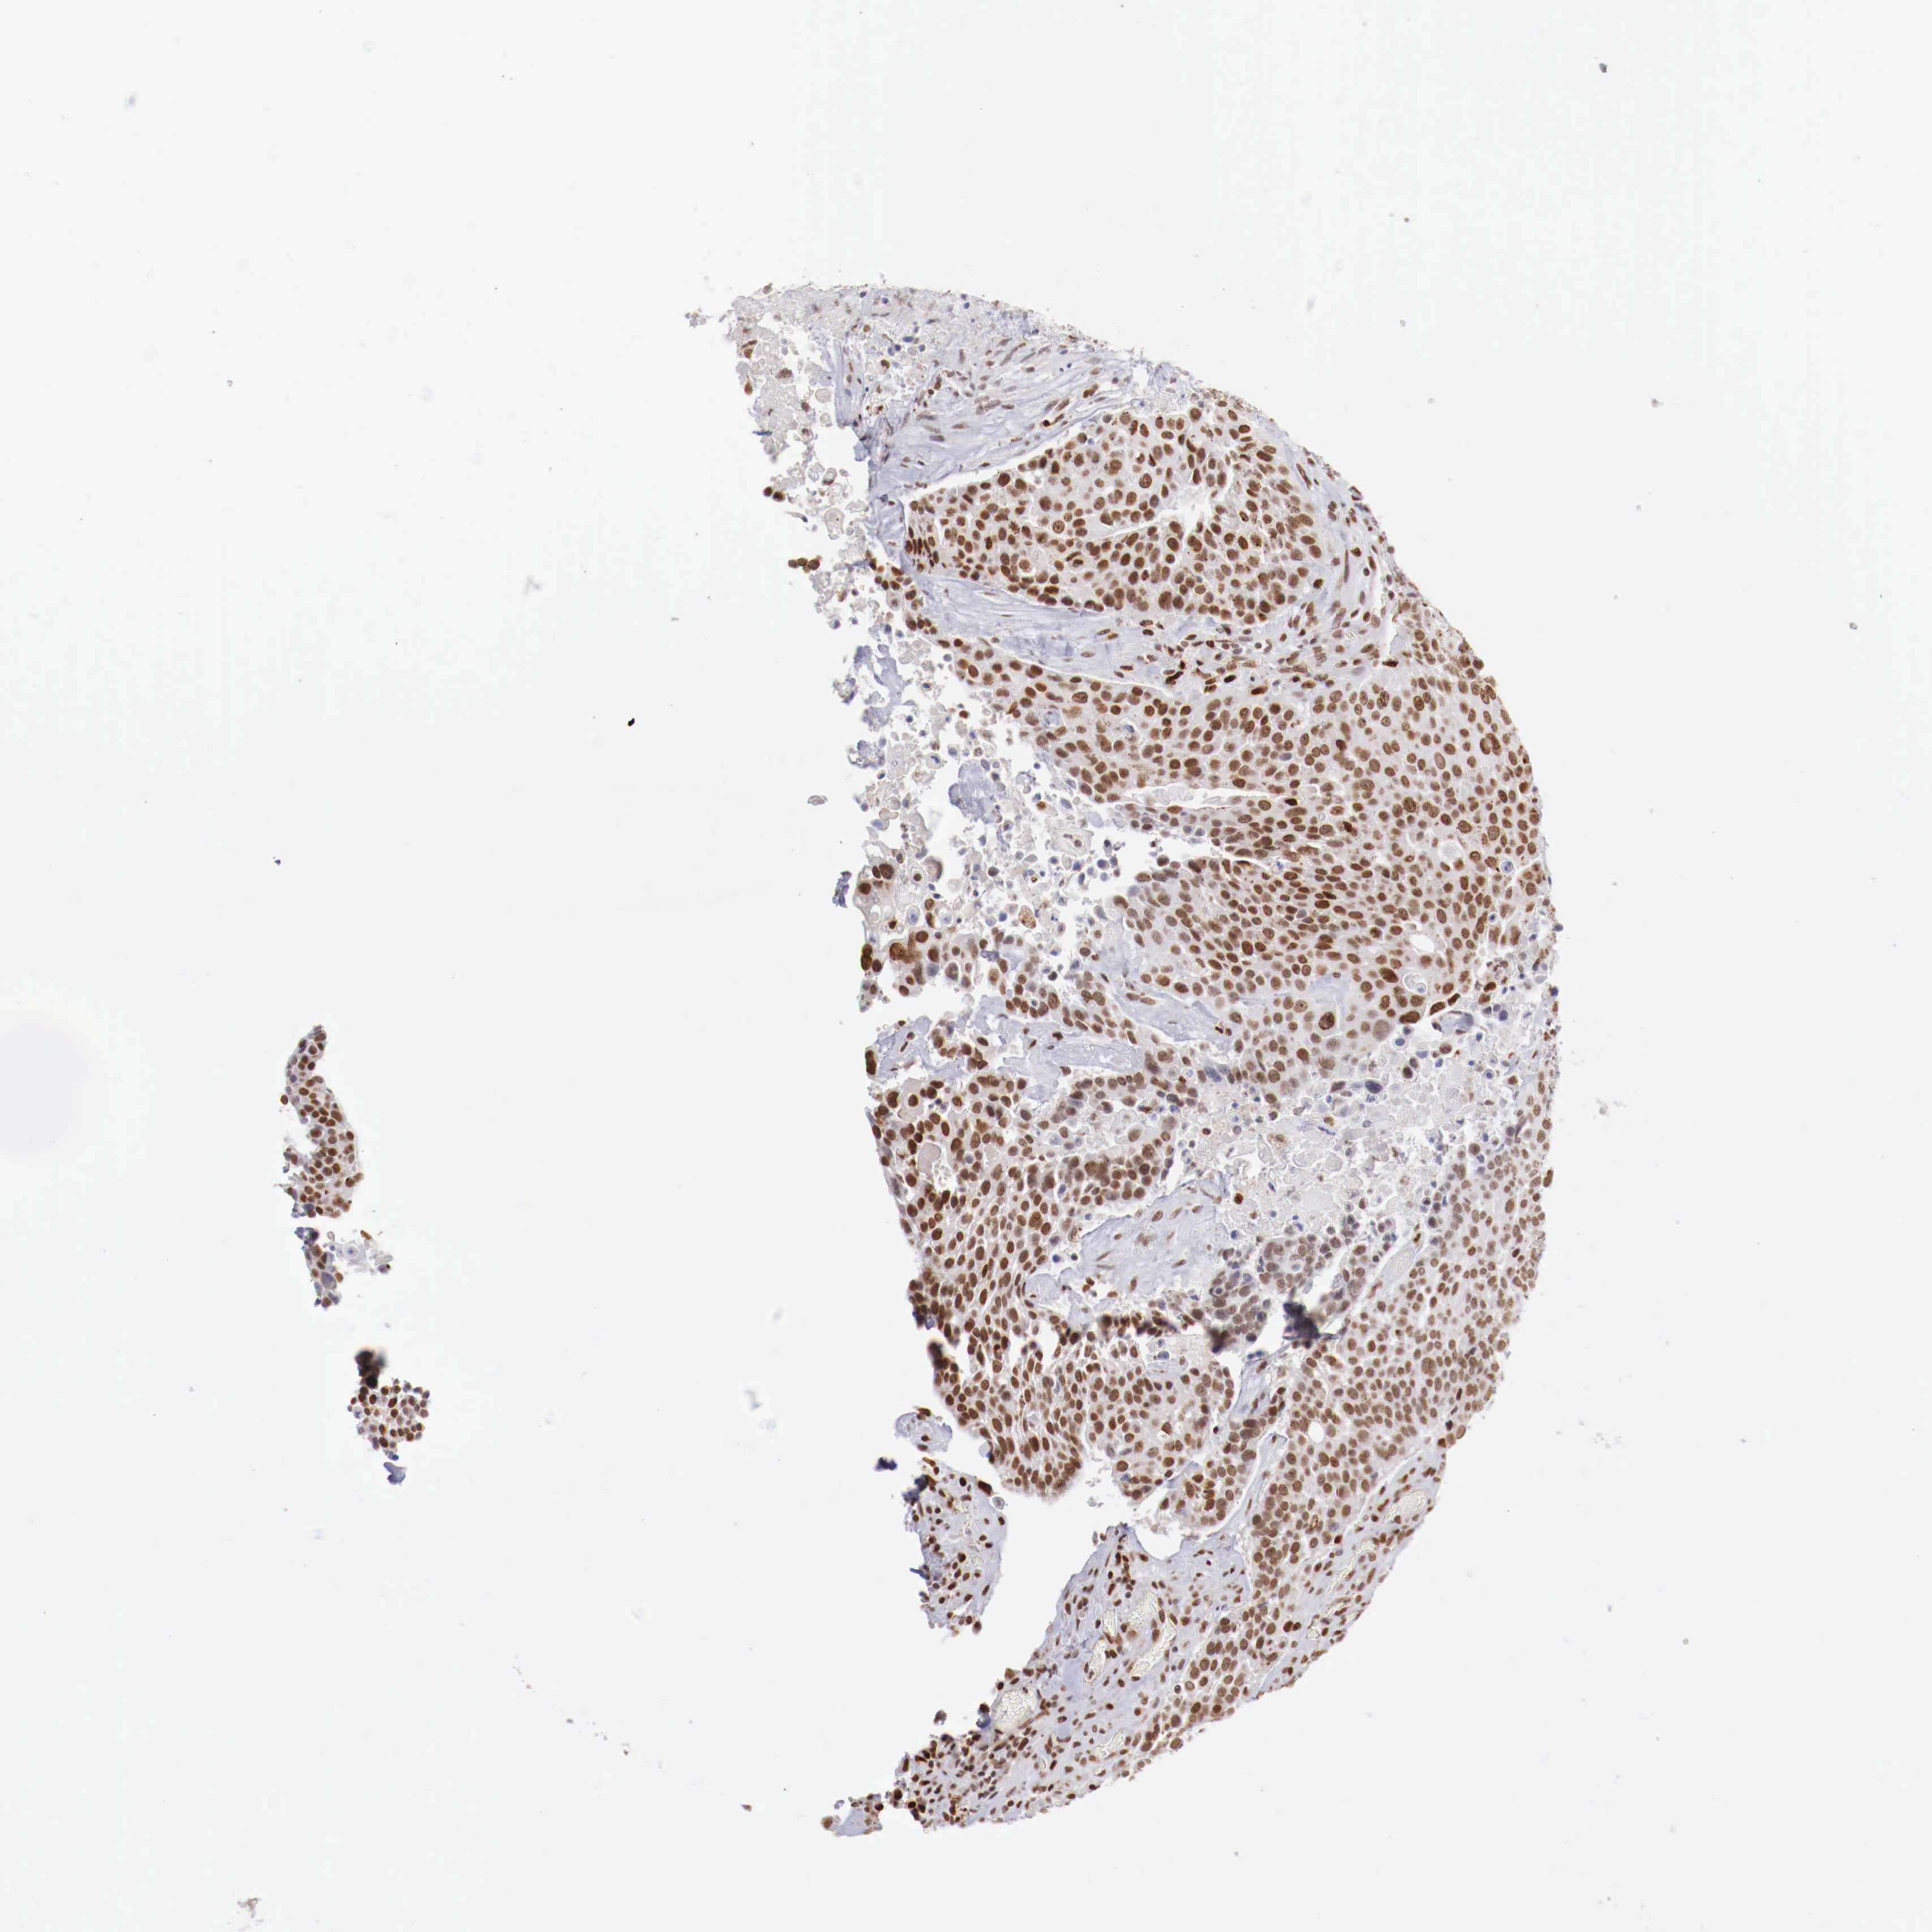

UROTHELIAL CANCER - Protein expressioni

A mouse-over function shows sample information and annotation data. Click on an image to view it in a full screen mode. Samples can be filtered based on level of antibody staining by selecting one or several of the following categories: high, medium, low and not detected. The assay and annotation is described here.

Antibody stainingi

Antibody staining in the annotated cell types in the current human tissue is reported as not detected, low, medium, or high, based on conventional immunohistochemistry profiling in selected tissues. This score is based on the combination of the staining intensity and fraction of stained cells.

Each image is clickable and will lead to virtual microscopy that enables deeper exploration of all samples and also displays staining intensity scores, fraction scores and subcellular localization as well as patient and tissue information for each sample.

Antibody HPA003474

Antibody CAB000328

Staining

High

Medium

Low

Not detected

Intensity

Strong

Moderate

Weak

Negative

Quantity

>75%

75%-25%

<25%

None

Location

Nuclear

Cytoplasmic/membranous

Cytoplasmic/membranous,nuclear

Urothelial carcinoma, High grade

Urothelial carcinoma, Low grade